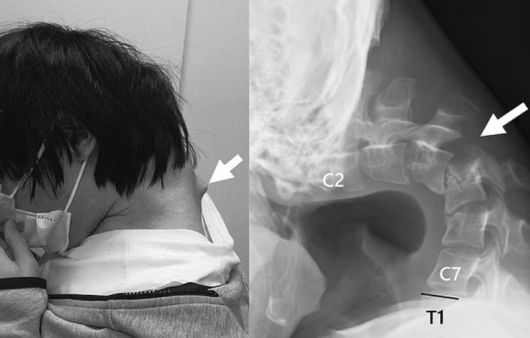

[파이낸셜뉴스] 하루에도 몇 시간씩 고개를 숙인 채 스마트폰으로 게임을 한 탓에 ‘머리떨굼 증후군’ 진단을 받은 20대 일본 남성의 충격적인 엑스레이가 공개됐다.

14일(현지시간) 영국 데일리메일은 “스마트폰으로 장시간 게임을 하면 무서운 ‘머리떨굼 증후군’이 발생할 수 있다는 사실이 드러났다”라며 일본 의료진이 공개한 25세 남성의 사례를 보도했다.

6개월 동안 목에 심각한 통증을 겪은 이 남성은 스스로 머리를 들어 올릴 수 없는 상태에 이르러 결국 병원을 찾았다. 뿐만 아니라 음식을 삼키기도 어려워 식사량이 줄었고, 그 결과 체중 역시 걱정스러울 정도로 감소한 것으로 알려졌다.

이 남성을 담당한 의료진은 활동적인 성격이었던 그가 10대 초반에 심각한 괴롭힘을 당한 뒤 학교를 그만 두고 몇 년 동안 방 안에 틀어박혀 지내면서 문제가 시작됐다고 설명했다. 이 남성은 매일 몇 시간씩이나 고개를 숙인 채 스마트폰으로 게임을 했고, 이러한 생활 습관이 그의 척추뼈에 악영향을 끼친 것이다.

결국 이 남성은 목뼈가 왜곡되고 탈구되었으며, 척추 부위에 흉터 같은 조직까지 증식한 상황에 처했다. 이에 의료진은 목을 고정하는 의료 기기를 이용해 교정을 시도했으나 남성이 감각 이상을 호소하면서 결국 수술을 선택하게 됐다.

의료진은 척추뼈에 생긴 흉터 같은 조직 중 일부를 제거하고, 목뼈에 나사와 금속 막대 등을 삽입해 자세를 교정했다. 수술 후 6개월 만에 이 남성은 머리를 수평으로 유지할 수 있게 됐으며 1년 뒤 추적 검사에서도 머리떨굼 증후군 증상이 재발하지 않았음이 확인됐다.